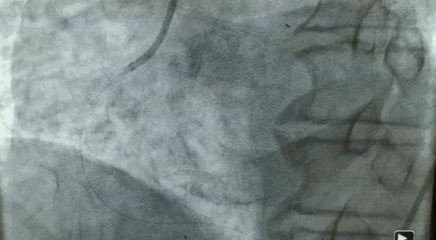

77岁男性,主动脉瓣重度狭窄,前降支及右冠严重钙化、迂曲并有狭窄,一月内频繁晕倒,病情危急。

第一个病人的特点是,需要在解决主动脉瓣问题的同时,解决冠状动脉的问题。针对病人特点,来永强教授和周玉杰教授提前在网上进行了会诊,设计一站式杂交手术,前降支和右冠各放一个支架,同时用SAPIEN 3瓣膜进行TAVR手术。

“相当于经皮主动脉瓣膜植入术中同时行PCI手术,不开胸,对患者来说是获得最大的效益。”周玉杰教授表示,TAVR同期行PCI,这两个手术合在一起,带来了病人的双获益。